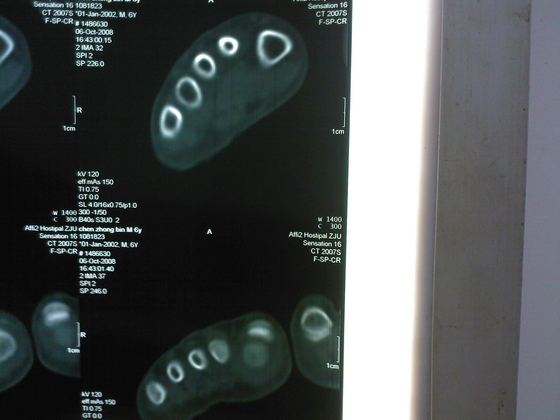

把病理送浙一医会诊后诊断为:骨外软骨瘤。同时做了CT检查。暂未予治疗。

今天把创面情况跟CT发上请大家看看。

继续发CT片